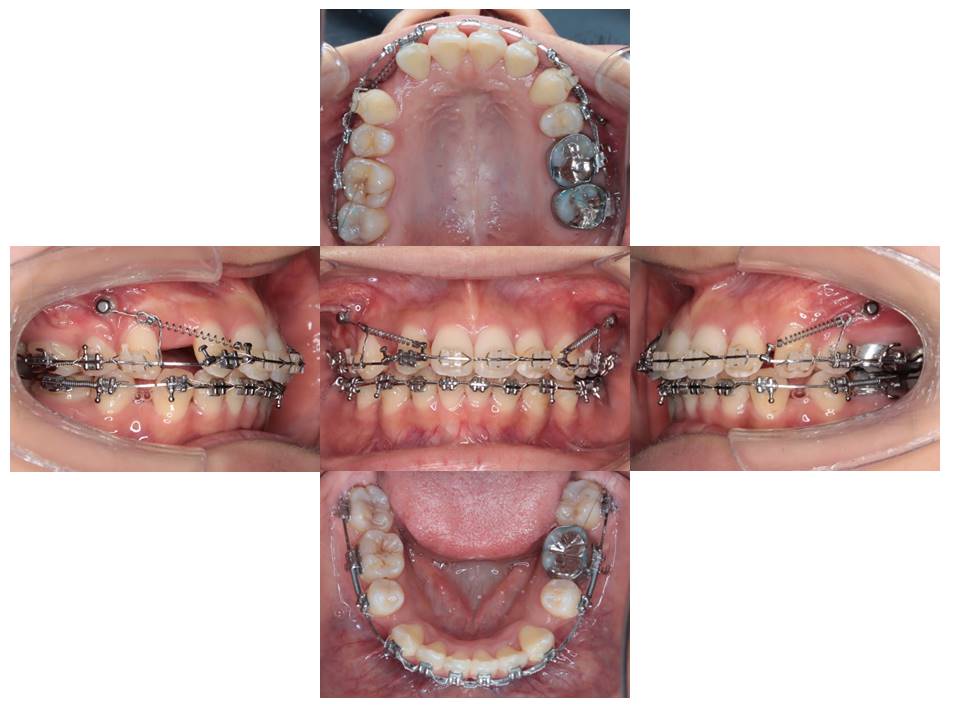

アンカースクリューを使用して上顎の前歯を後方移動しています